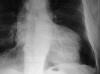

Fibrosis pulmonar. ICC.